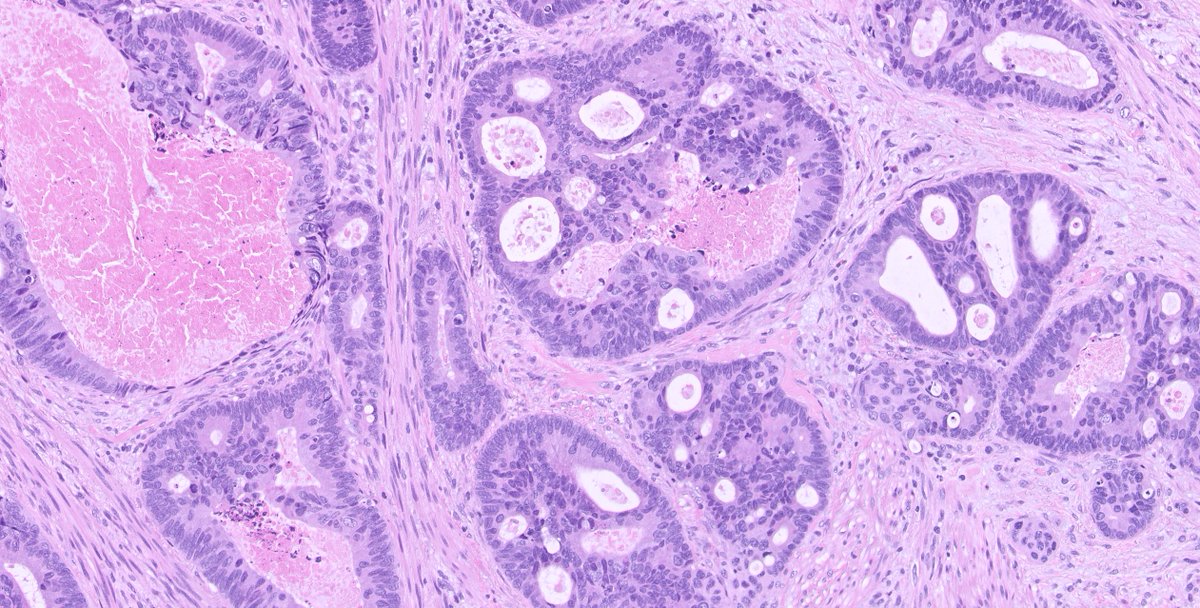

1/ A #GUpath case...TURB specimen with the following histology ๐Ÿ‘‡๐Ÿ‘‡๐Ÿ‘‡ Tumor at the urinary bladder neck. IHCs in the thread. Your dx? #pathology #PathTwitter